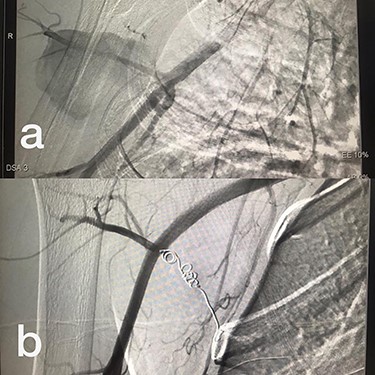

Sites of injury included 6 Posterior Tibialis arteries (27.2%) (Fig. 1), 2 deep femoral arteries (9.09%), 2 Superficial femoral arteries (9.09%) and 2 maxillary arteries (9.09%). We had only one injured artery (4.54%) in each of the following sites: internal pudendal a., Axillary a. (Fig. 2), Proneal a., Lumbar a., External carotid a., Anterior Tibialis a., common iliac a. (Fig. 3), temporal a., Thoracic aorta and Internal iliac artery (Fig. 4).

(a) Branch of Axillary artery before intervention, (b) after coil embolization.